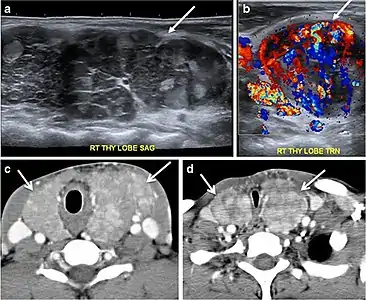

Fig. 4. A 45-year-old male patient presented with anterior mediastinal metastatic PTC lesions and occult primary on imaging. Histopathology examination of the resected thyroid gland revealed micro-foci of PTC; the largest, in the isthmus, measured 4 mm. a transverse greyscale ultrasound of the thyroid demonstrates homogeneous gland with normal echogenicity and size. No focal lesion or micro-calcifications. b Non-enhanced CT scan obtained as part of PET/CT examination shows a heterogeneous, large, relatively dense anterior mediastinal mass (white arrow) with peripheral calcification (arrowheads). Thyroid gland has normal CT appearance with no abnormal FDG uptake (not shown).[1]

Fig. 14. A 19-year-old male patient known to have multi-nodular goiter and FNA, showing underlying Hashimoto's thyroiditis. a, b Sagittal and transverse greyscale and colour Doppler ultrasound of the neck demonstrate a hypoechoic enlarged right thyroid lobe with small hyperechoic regenerative nodules and marked hypervascularity (white arrows). c, d Enhanced axial CT scan images of the neck demonstrate a heterogeneously enhancing and enlarged thyroid gland, left more than right lobe, and the trachea is markedly narrowed.[1]